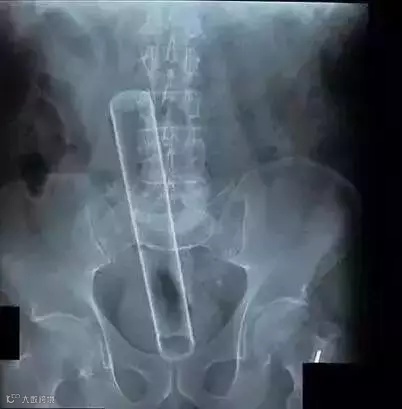

玻璃棒▽

扳手▽

擀面杖▽

十斤重的哑铃▽

钥匙▽

手电筒▽

这些本不该出现在肛门内的东西,总有人会“一不小心”塞进去了,这对菊花来说是很大的一种伤害。

不仅会导致菊花失去弹性,还可能造成菊部地区破裂。

菊花周围的皮肤,最大的耐受尺寸直径是2cm,超过这个数,就很可能会肛裂。